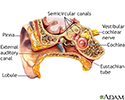

It is not known exactly what causes a person to "hear" sounds with no outside source of the noise. However, tinnitus can be a symptom of almost any ear problem, including:

- Meniere disease -- an inner ear disorder that involves hearing loss and dizziness

- Problem with the eustachian tube (tube that runs between the middle ear and the throat)